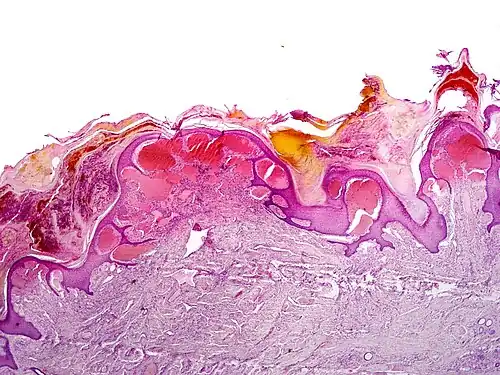

Angiokeratomas characteristically have large dilated blood vessels in the superficial dermis and hyperkeratosis (overlying the dilated vessels).

Scrotal angiokeratoma; visible large dilated blood vessels and hyperkeratosis -